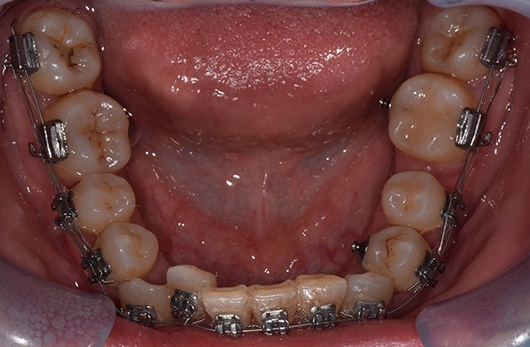

第二个case是已经开始矫正了一年半,当初智齿还是阻生的,但角度很好,经过矫正,今天黏上颊面管,纳入矫治,已经变废为宝了,六龄齿的间隙快要被完全关闭了。这样做当然比拔除两个第一前磨牙排齐所费周章,但能多保留两个天然健康的牙齿,也是一辈子收益的。